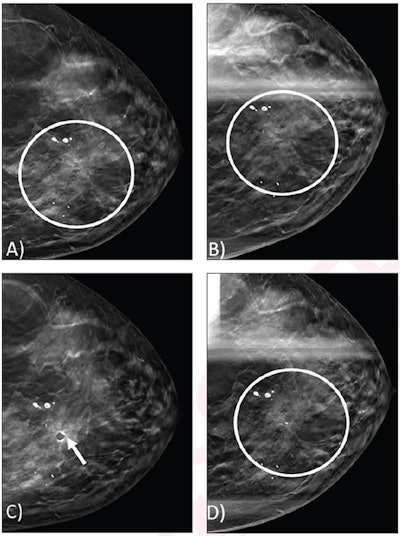

(A) Craniocaudal view from screening DBT mammogram shows architectural distortion (circle) in the upper inner position, which was not detected by digital mammography (not shown). (B) Spot craniocaudal view from subsequent diagnostic DBT mammogram shows persistence of architectural distortion (circle). No ultrasound correlate was identified (not shown). Core needle biopsy of the architectural distortion was performed, yielding a radial scar without atypia. (C) Post-biopsy mammogram shows cylinder clip (arrow) in appropriate position. Biopsy result was considered concordant, and patient underwent recommended imaging surveillance. (D) Spot craniocaudal view from diagnostic mammogram performed 12 months later shows stable appearance of an architectural distortion (circle).(A) Craniocaudal view from screening DBT mammogram shows architectural distortion (circle) in the upper inner position, which was not detected by digital mammography (not shown). (B) Spot craniocaudal view from subsequent diagnostic DBT mammogram shows persistence of architectural distortion (circle). No ultrasound correlate was identified (not shown). Core needle biopsy of the architectural distortion was performed, yielding a radial scar without atypia. (C) Post-biopsy mammogram shows cylinder clip (arrow) in appropriate position. Biopsy result was considered concordant, and patient underwent recommended imaging surveillance. (D) Spot craniocaudal view from diagnostic mammogram performed 12 months later shows stable appearance of an architectural distortion (circle).ARRS